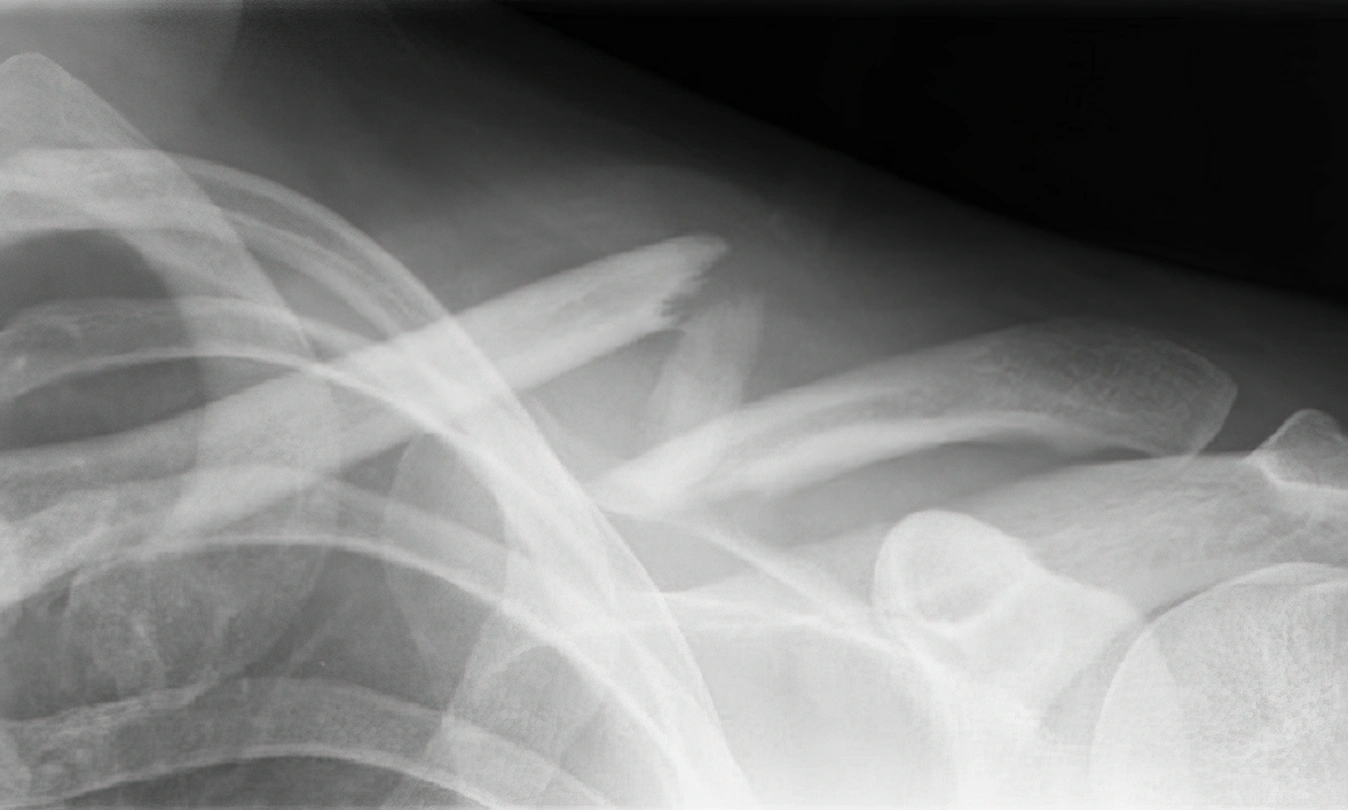

Prelom ključne kosti

Prelom ključne kosti je obično posledica pada i najčešći je kod mlađih, aktivnih osoba. Ključna kost ima veliki potencijal zarastanja pa je uobičajeni tretman konzervativni – ruka u trougloj marami (mitela). Operativni zahvat se preporučuje u slučajevima velike deformacije na mestu preloma, višestrukih (kominutivnih) preloma ili kada je ugrožena koža pa preti opasnost od prelaska u otvoreni prelom.

Prelom ključne kosti (klavikule), rendgenski snimak